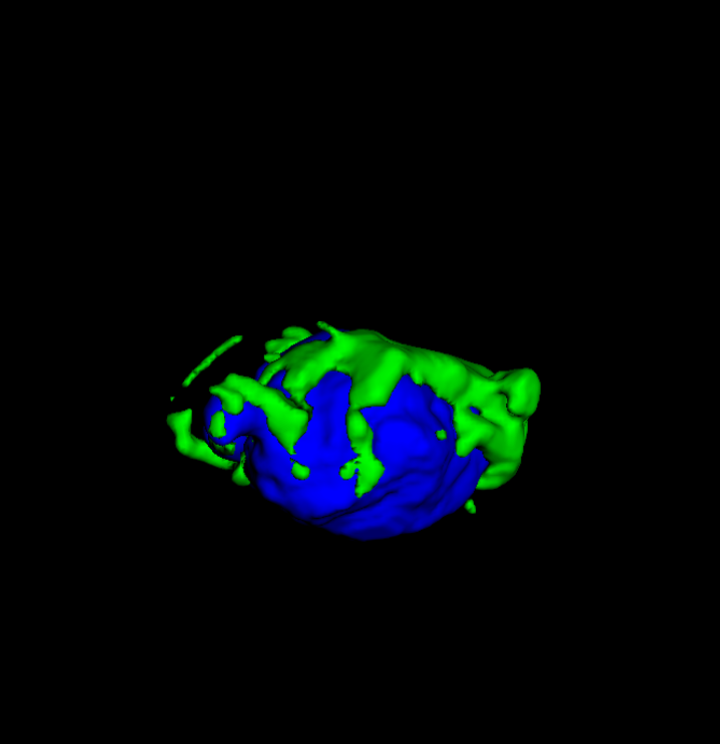

Tumour Information Preservation. For the brain tumor segmentation, we use a Swin UNETR model[28, 70], trained with random rotation, and intensity as data augmentation. On the test set with human ground-truth annotations (), the brain volumes generated from single slice input preserve the volume of the different tumour components (paired t-test, for all 3 classes). In Figure 4, we highlight the tumor profiles of the generated MRIs compared to the ground truth tumour profile. The real MRI Dice score in the test set is 85.15 while the generated MRIs from a single slice have a dice score of 83.09. This shows how the generated MRIs indeed preserve the tumor information and can act as an affordable and informative pseudo-MRI, before conducting an actual costly MRI examination in hospitals. More detailed results are provided in supplementary material.

On the test set with human ground-truth annotations (), the brain volumes generated from single slice input preserve the volume of the different tumour components (paired t-test, for all 3 classes) (see Table I). The real MRI Dice scores are put for reference to our generated MRIs. X-Diffusion outperforms baselines TPDM [39] and ScoreMRI [19] in tumour preservation (see Table I and Figure III). We ran experiments comparing the tumour segmentation Dice Score varying X-Diffusion configurations. The multi-slice input X-Diffusion achieves marginally better Dice Score than the single slice input model (83.47 83.09). We also ran experiments with slice input used for volume reconstruction intersecting or not with tumour. We observe on average a drop of 6% Dice Score (see Table I). Further away from the tumour the input slice for volume reconstruction is selected, we observe a linear decrease in tumour segmentation Dice Score with lowest value of 77.21 Dice Score (see Figure VI).